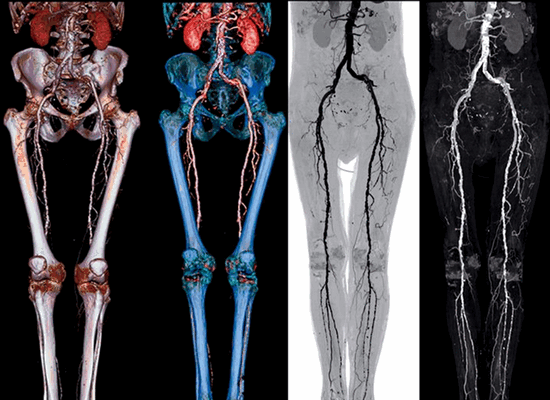

Компьютерная томография (КТ) сосудов, или КТ-ангиография - это исследование, которое делается с помощью мультиспирального компьютерного томографа (МСКТ) и применяется для визуализации крупных кровеносных сосудов (главным образом, артерий) с целью выявления их патологических изменений. Любое медицинское отображение сосудов называется ангиографией, и наряду с КТ-ангиографией существуют еще классическая субтракционная ангиография (ДСА, DSA), которая выполняется в условиях рентген-операционной, и МР-ангиография - это исследование делается на магнитно-резонансном томографе.

КТ сосудов применяется для оценки состояния самых разных сосудов организма. В основном, речь идет об артериях - сосудах, приносящих кровь к органам. В случае закупорки сосудов, нарушения кровотока по ним, или изменений сосудистой стенки КТ-ангиография выявляет различные патологические признаки. Чаще всего КТ артерий применяется перед операцией устранения атеросклеротических бляшек или тромбов - в качестве одного из этапов предоперационной подготовки. Например, это исследование демонстрирует хирургу наличие атеросклеротических бляшек, стенозов и окклюзий крупных артерий, помогает точно оценить диаметр сосудов и т.п.

КТ-ангиография выполняется с целью оценки сосудов:

- нижних и верхних конечностей - при атеросклерозе

При КТ ангиографии появляется возможность различить артериальные и венозные сосуды (КТ-артериография/КТ-венография), оценить их ход и извитость, наличие атеросклеротических бляшек и тромбов, наличие аномалий и аневризм, повреждения сосудов (в результате травмы или операции), оценить кровоснабжение опухолей перед их эмболизацией. Рассмотрим несколько примеров.

Что выявляет КТ-ангиография. Патологическая извитость внутренних сонных артерий в шейном сегменте (С1). Хорошо виден ход сосудов, можно оценить их диаметр, состояние стенок. Трехмерная (3D) реконструкция сосудов.